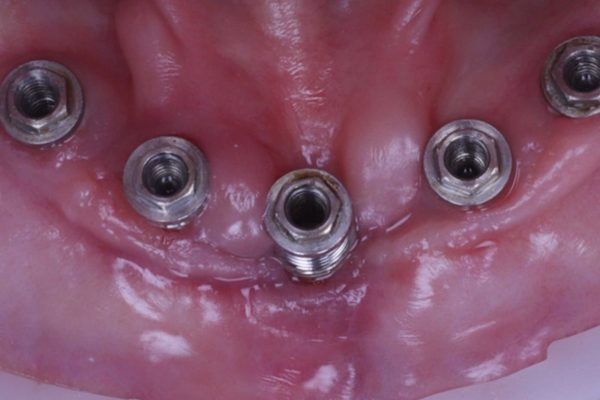

When the implant bridge was off, I was able to irrigate the area and remove the soft plaque deposits present (Figures 5 and 6).